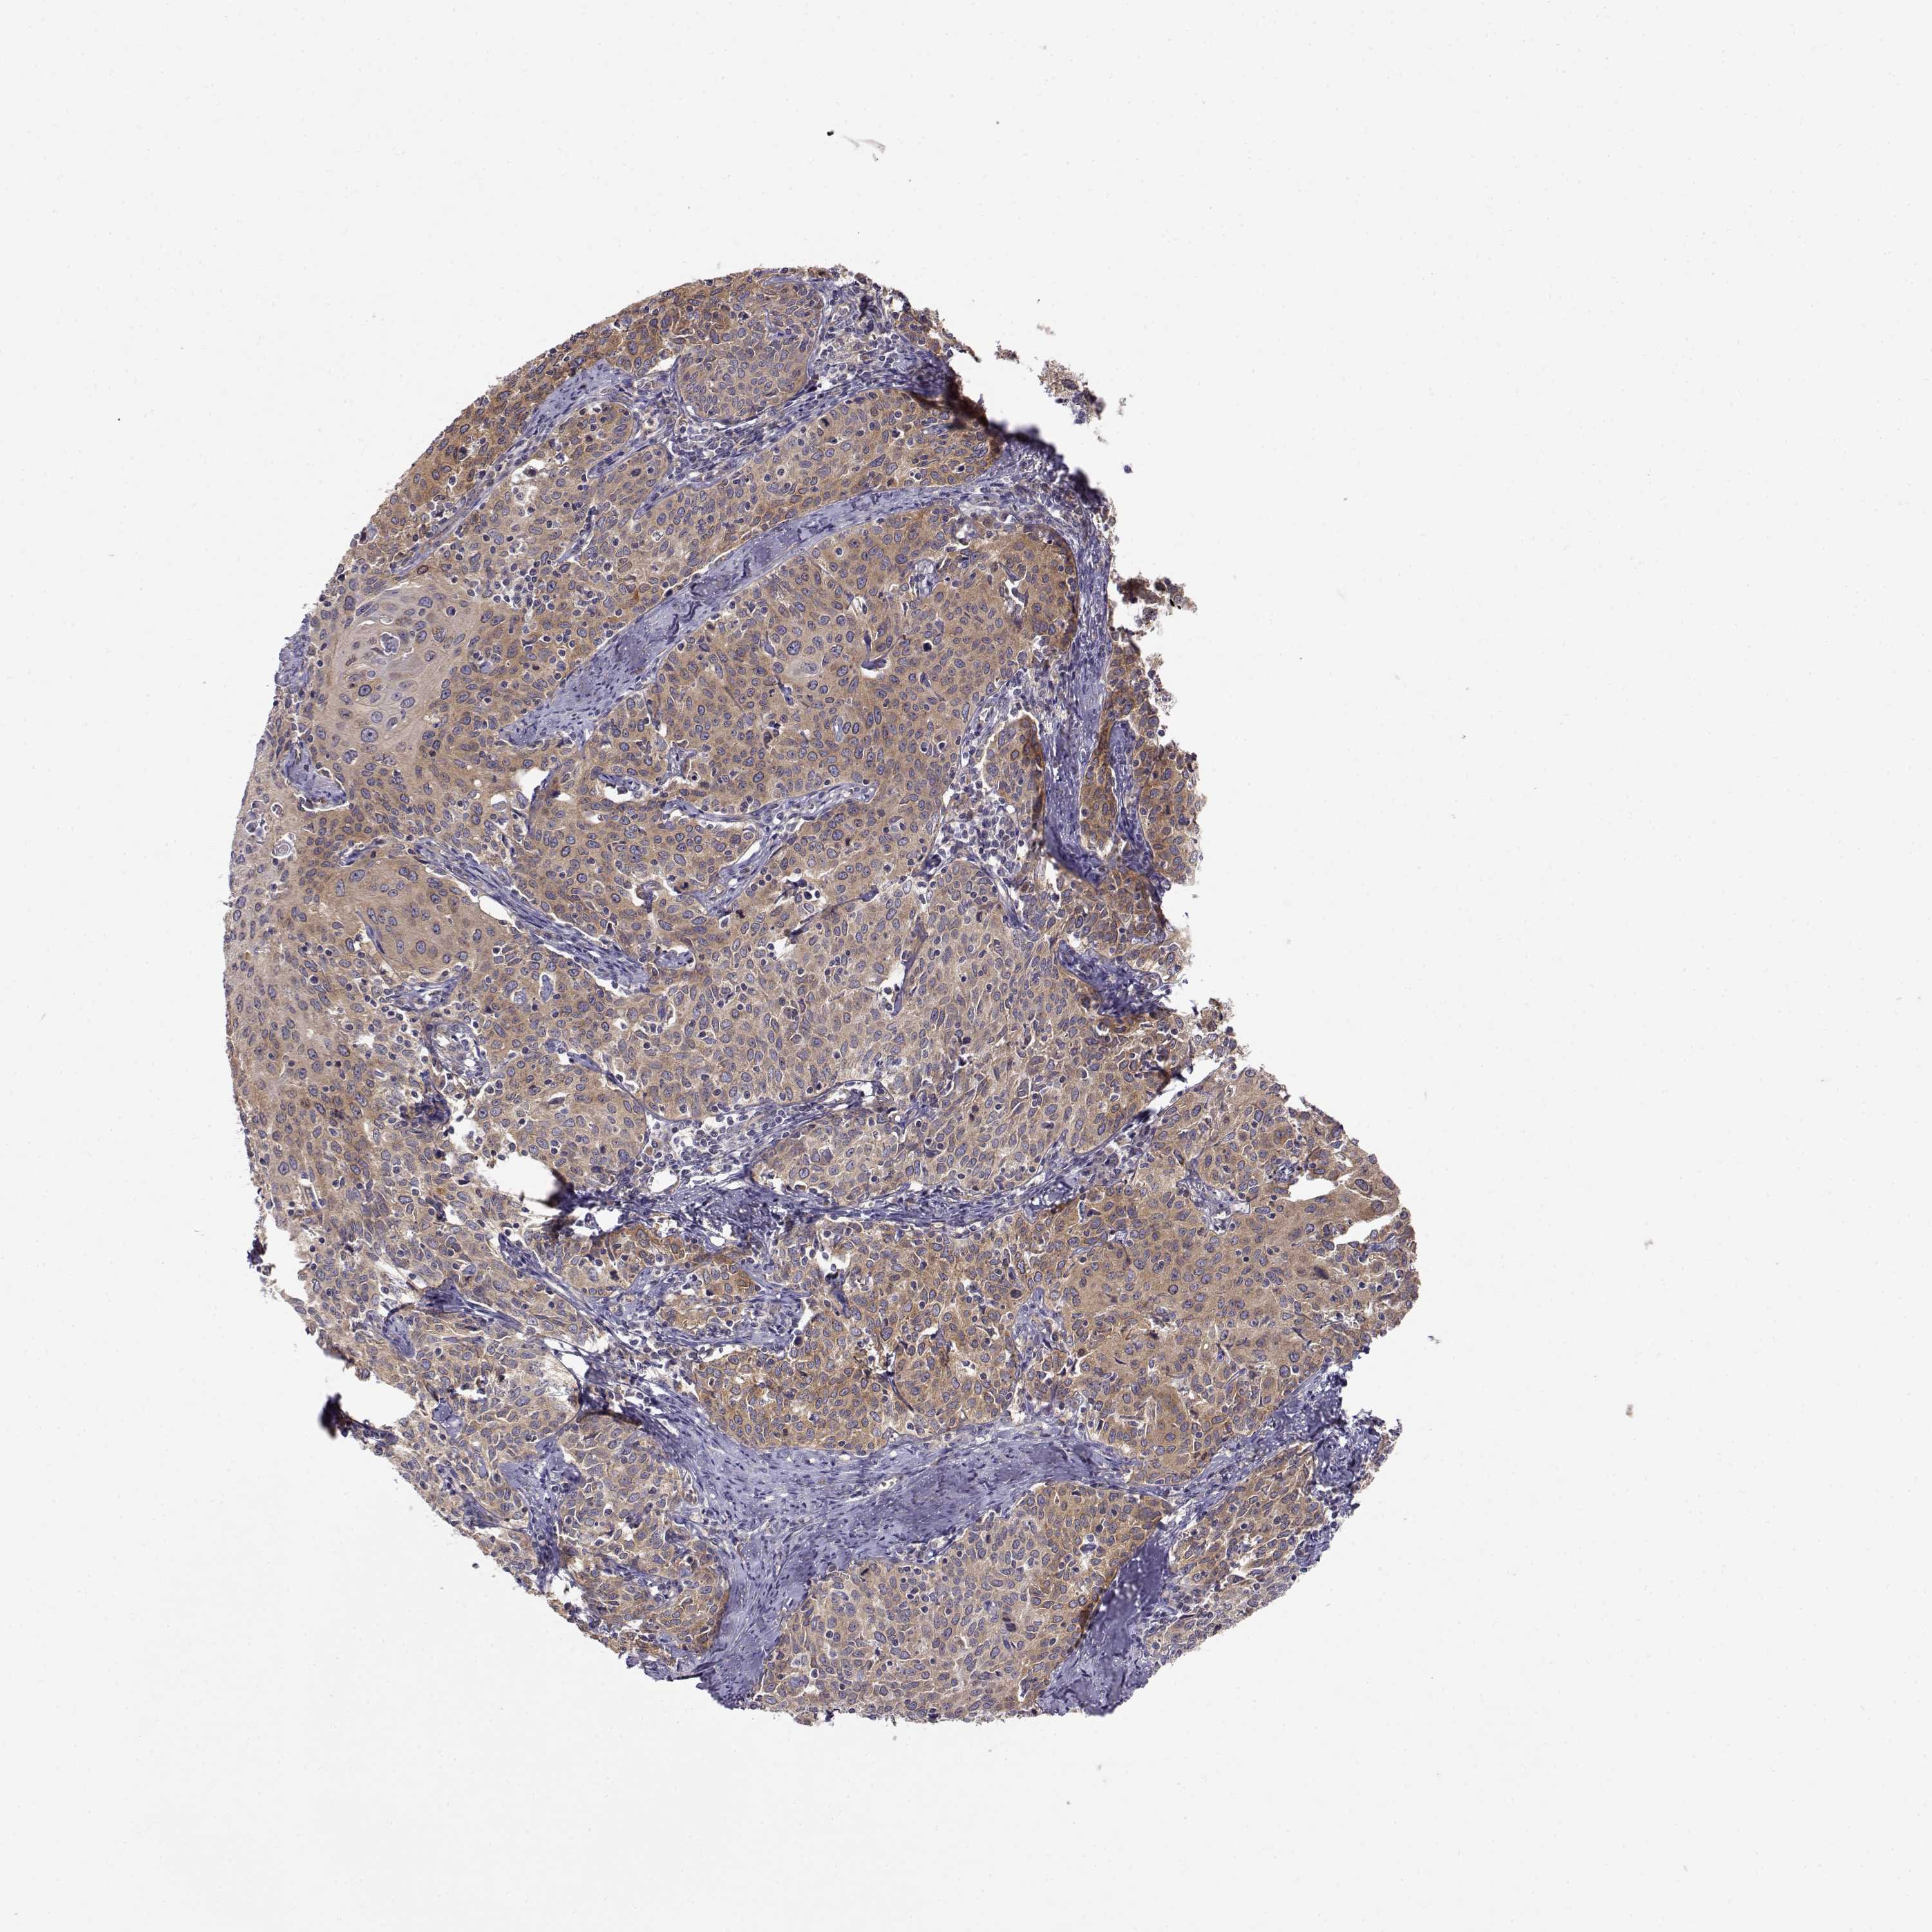

CERVICAL CANCER - Protein expressioni

A mouse-over function shows sample information and annotation data. Click on an image to view it in a full screen mode. Samples can be filtered based on level of antibody staining by selecting one or several of the following categories: high, medium, low and not detected. The assay and annotation is described here.

Note that samples used for immunohistochemistry by the Human Protein Atlas do not correspond to samples in the TCGA dataset.

Antibody stainingi

Antibody staining in the annotated cell types in the current human tissue is reported as not detected, low, medium, or high, based on conventional immunohistochemistry profiling in selected tissues. This score is based on the combination of the staining intensity and fraction of stained cells.

Each image is clickable and will lead to virtual microscopy that enables deeper exploration of all samples and also displays staining intensity scores, fraction scores and subcellular localization as well as patient and tissue information for each sample.

Antibody HPA073653

Staining

High

Medium

Low

Not detected

Intensity

Strong

Moderate

Weak

Negative

Quantity

>75%

75%-25%

<25%

None

Location

Nuclear

Cytoplasmic/membranous

Cytoplasmic/membranous,nuclear

Squamous cell carcinoma, NOS

Adenocarcinoma, NOS